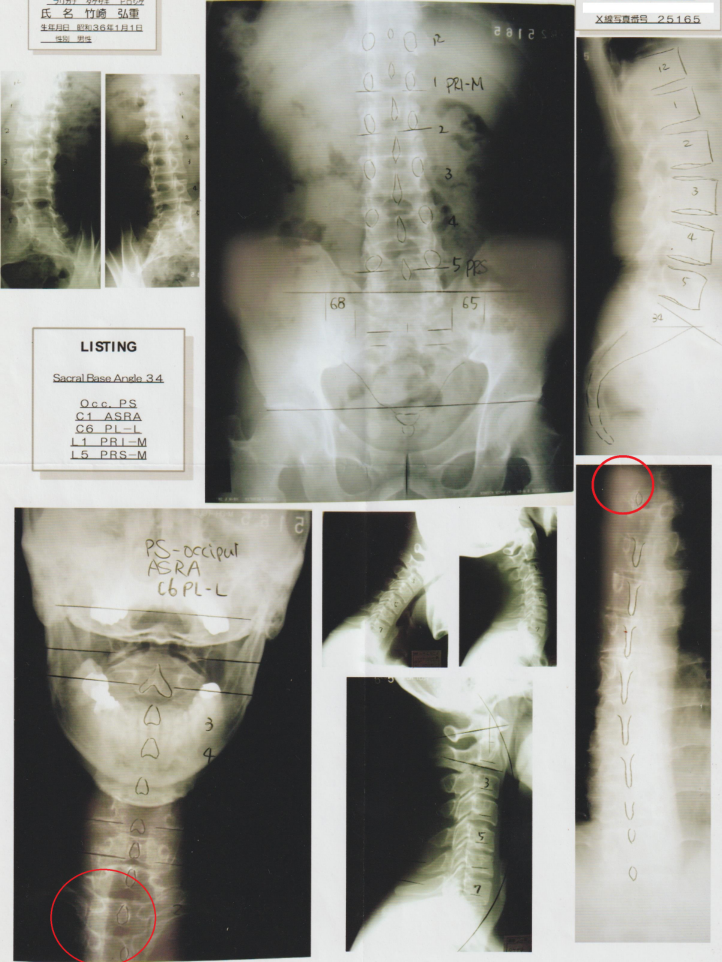

上の左側の写真を見てください。自分としては真っすぐの姿勢感覚ですが、ご覧の通り左肩が下がっています。真ん中の写真を見ていただくと判りますが、胸椎2番部に、いわゆる「ズレ」があるからです。骨の変形はありませんが、この部位の靭帯・筋肉の部分断裂があります。これは、治る事はありません。

(後ろからの写真は頭を下げているため、右肩が下がって写っています。)

私の全身レントゲン写真 赤丸の部位が、胸椎2番と3番の部分です

カイロプラクティック療法でのレントゲン分析は、立位姿勢の全身像を撮影して分析し、施術個所を特定して行います。

これでも、「気を付け」の立位姿勢で写したもので、第5腰椎と第2胸椎・頸椎6番に著明な変位があり、とても分かりやすい見事なストレートネッグです。

骨に異常はありませんが、骨を支える筋肉靭帯に問題があります。これでも整体の学校で、下手ながらもバキボキと練習したおかげで、改善された状態です。